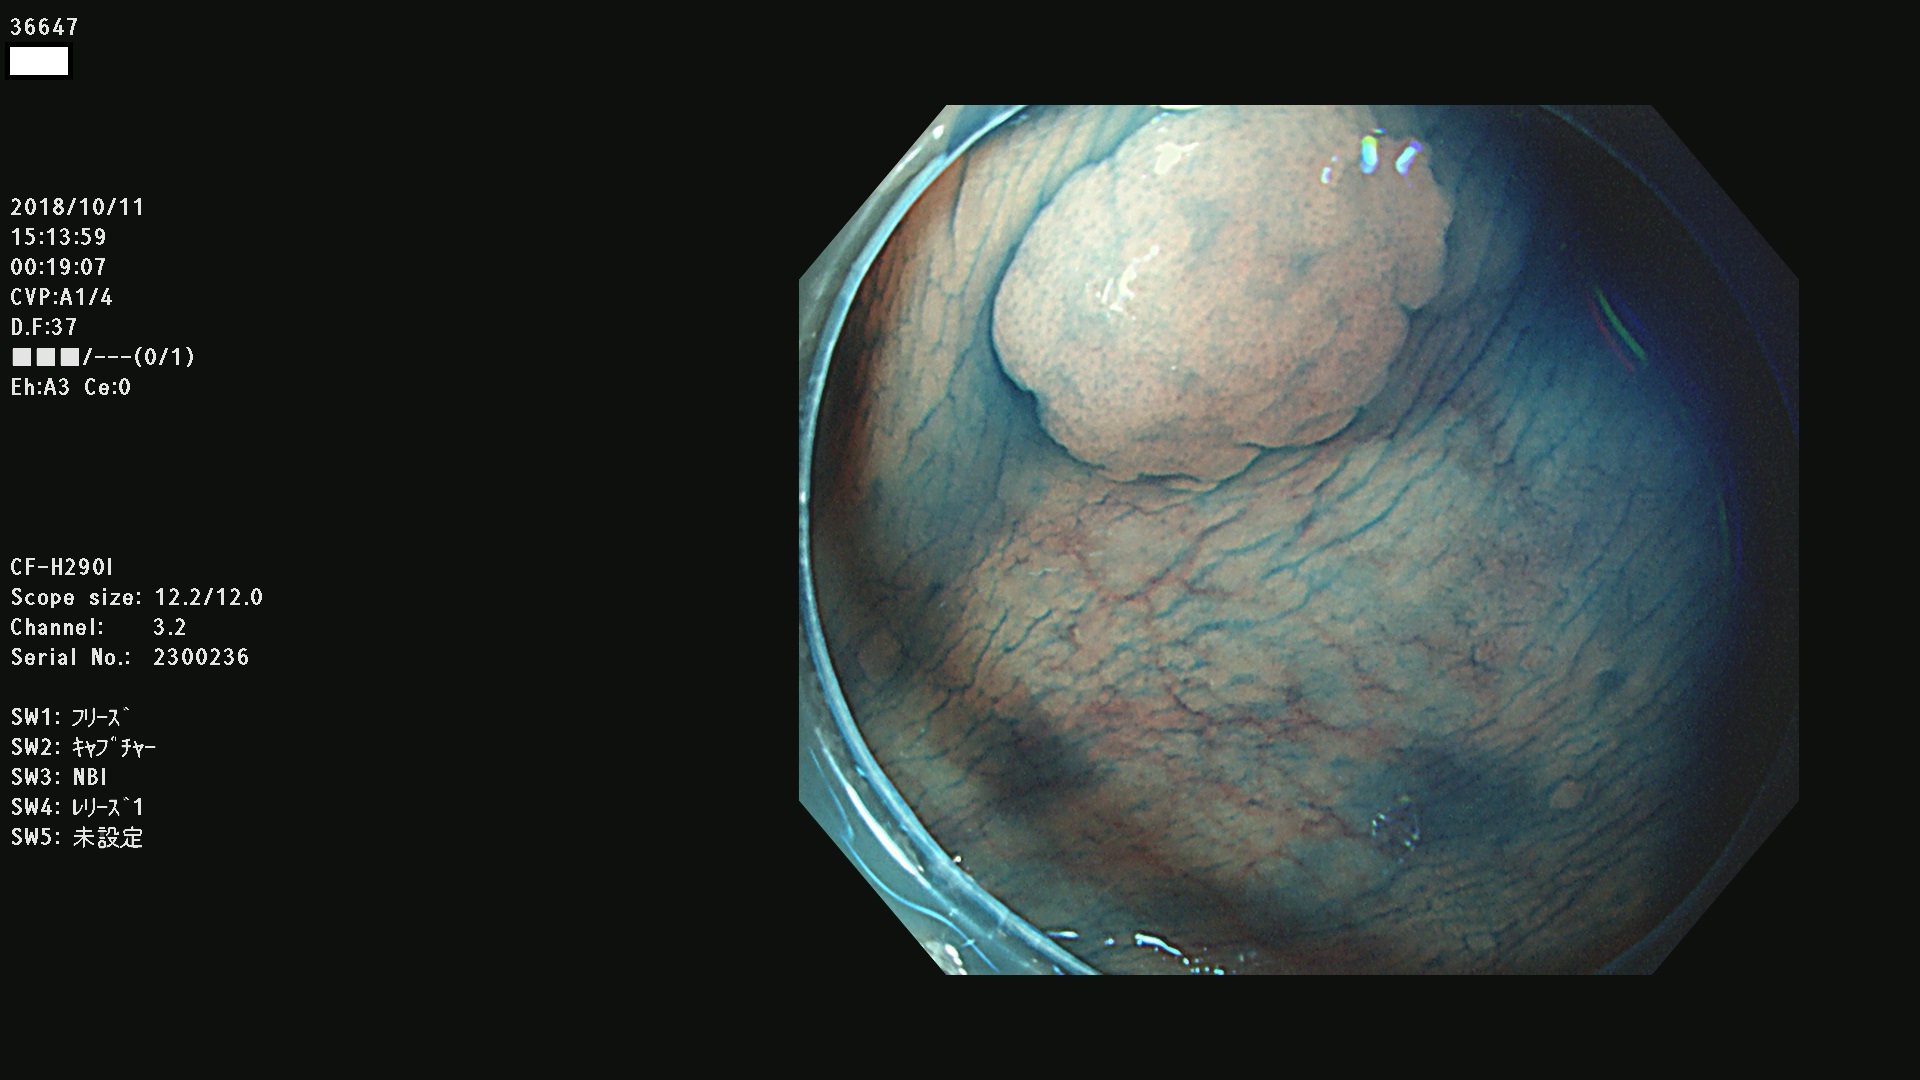

36600 36601 36603 36605 36606 36608 36609 36610 36611 36612 36613 36615 36617 36620 36621 36624 36625 36626 36627 36628 36629 36631(SSAPのみ) 36632 36633 36634 36636(SSAPのみ) 36637(SSAPのみ) 36639 36640 36642 36643 36644 36646 36647 36648 36649(SSAPのみ) 36650(SSAPのみ) 36652 36653 36654 36655(SSAPのみ) 36656 36657 36658 36659 36660 36661(SSAPのみ) 36665 36668 36669 36672 36673 36676 36677 36678 36679 36681 36682 36683 36684 36685 36687(SSAPのみ) 36691 36692 36693 36694 36695 36696 36697 36699(SSAPのみ)

発見困難で危険性の高い平坦型病変(上記100名より抽出)